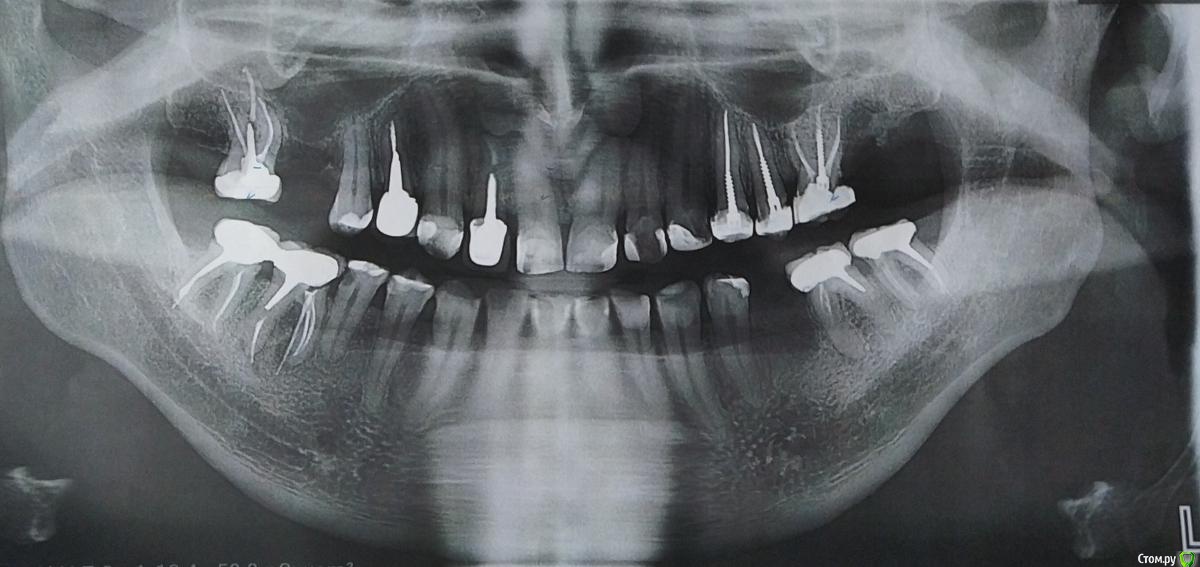

Ljocha Опубликовано 5 августа, 2020 Поделиться Опубликовано 5 августа, 2020 (изменено) доброго времени суток! недавно перелечили каналы и поставили коронки на 1.7, 3.6, 3.7, 4.6, 4.7 сделал КТ в другом месте, по которому врач-хирург сказал3.7 - перфорация корня, удаление 4.6 - удаление https://dropmefiles.com/77eRU врач-ортопед там где делали не соглашается с этим, говорит что после перелечивания стало лучше вопрос к ортопедам: "лечить нельзя, удалить" или "лечить, нельзя удалить"или обе точки зрения имеют место быть Изменено 5 августа, 2020 пользователем Ljocha Ссылка на комментарий

Ljocha Опубликовано 5 августа, 2020 Автор Поделиться Опубликовано 5 августа, 2020 вот к примеру 3.7 по ОПТГ пару недель после перелечивания и окоронивания: а это совсем свежий снимок, 5 дней до была имплантация 3.5: Ссылка на комментарий

chervoncevdaniil Опубликовано 5 августа, 2020 Поделиться Опубликовано 5 августа, 2020 (изменено) 17 47 судя по снимку перелечены нормально,проблемы могут быть впоследствии с 46 и 36 и 37,ортопед который делал коронки видел панорамный снимок после пломбировки каналов до изготовления коронок или он был уже сделан для планирования имплантации и ортопед увидел его уже после протезирования? Изменено 5 августа, 2020 пользователем chervoncevdaniil Ссылка на комментарий

Ljocha Опубликовано 5 августа, 2020 Автор Поделиться Опубликовано 5 августа, 2020 chervoncevdaniil ОПТГ было сделано для имплантации,в последствии один из терапевтов видел снимок и проговорился что там и там не годится,потом начал изучать вопрос со всем занудством,показывать другим врачам и вылез целый ворох проблем, все картинки что выше врач-ортопед, проводивший это лечение (5 коронок) видел удаленно, серьезные проблемы отказывается видеть,хирург "рядом" тоже все ответы вида: "я думаю что все станет только лучше, главное качественно перелеченные каналы" хочу добавить что это зубы все резорцин-формалиновые, были депульпированы давно и слеплены на штифтах, в поликлинике полностью за деньги было:1. вынуты штифры и перелечены каналы 1.7, 3.7, 3.6, 4.6, 4.7;2. удалены 1.6 и 3.5;3. поставлена металокерамика 1.7, 3.7, 3.6, 4.6, 4.7;4. после установки коронок сломался штифтовой 2.7 пришлось удалить;5. поставлен имплант mis seven на место 3.5; уважаемый хирург Bier говорит что почти все удалять,там где лечили - более оптимистичны это все ради одного: понять дурят ли меня (они получается заинтересованы т.к. за все уплачено немало денег) или действительно такой подход имеет место быть Ссылка на комментарий